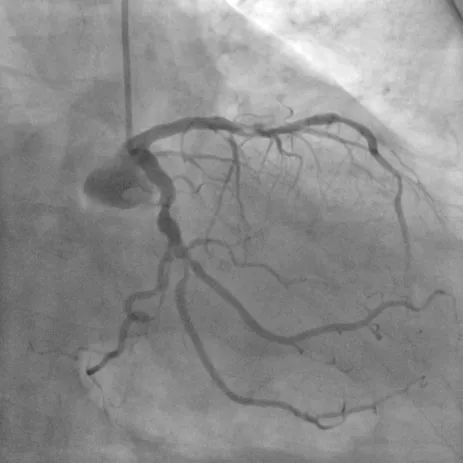

造影图:

造影显示提示前降支严重狭窄、回旋支次全闭塞、右冠慢性闭塞。

先后分期完成右冠及左冠PCI手术,但右冠CTO病变PCI手术术中出现开口夹层,一直撕裂至后三叉,且导丝位于假腔内。